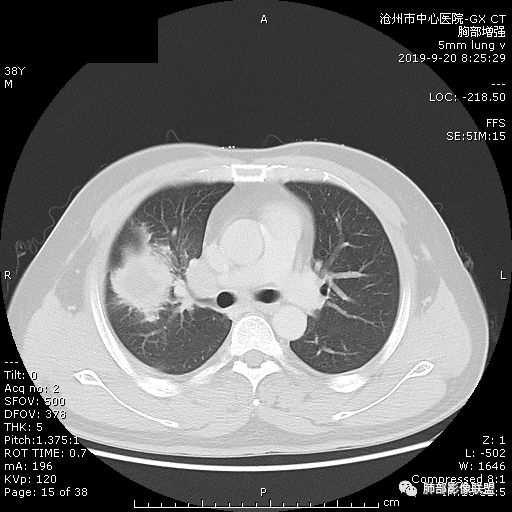

青年男性,肿瘤指标无异,右上中肺团片影,形态不规,跨叶生长,

病灶内见坏死,增强边缘强化,考虑炎性肉芽肿,TB,鉴别鳞。

年轻男性,咳嗽2月,痰中带血,胸痛,炎症指标稍高,肿标正常。影像,右肺上叶不规则团块影,浅分叶,伴边界不清磨玻璃影,从外周向内分布,局部胸膜增厚,病灶中央坏死,坏死边界尚清,空洞形成,空洞内壁光滑;考虑炎性肉芽肿性病变,结核可能,鉴别恶性肿瘤及真菌感染。病灶分布特点不考虑隐球。

右肺上叶不规则病灶,密度不均,有分叶,边缘不清,中央有坏死,坏死壁尚光滑,增强壁有强化,病灶有外朝内,整体收缩为主,慢性病程,考虑炎性病变,肺脓肿或者结核,淋巴结肿大,支气管截断,胸膜脂肪间隙变窄,加个鉴别恶性肿瘤。

右上肺占位,总体膨胀性生长,支气管截断,坏死明显,常规考虑鳞。

38岁,男性,慢性咳嗽2月,右胸痛8天,无发热;白细胞高,肿瘤标志物不高;右上肺不规则块状影,周围有磨玻璃影,边界清,整体有膨胀感,分叶,与胸膜糊墙,并见栽赃,增强肿块中央坏死,周边强化。综合考虑,考虑恶性,鳞癌可能。

38岁,男性,慢性咳嗽2月,右胸痛8天,无发热。白细胞高,肿瘤标志物不高。右上肺不规则块状影,周围有磨玻璃影,边界模糊,整体有膨胀感,分叶,与胸膜糊墙,可疑栽赃,增强肿块中央坏死,边界清,周边强化明显,强化区有低密度影,壁不规则,跨叶生长,支气管截断,伴支气管扩张,综合考虑腺癌

中年男性,咳嗽2月,伴胸痛8天,少许痰血,无发热中性粒明显增高,低氧,肿标不高,右肺上叶不规则实性肿块,深分叶,局部凹陷呈月牙铲改变,多坏死,多空泡,前段支气管分支似见堵塞,2R、4R、10R和7区淋巴结肿大。考虑肺癌可能,建议支气管镜活检

晨读病例,右肺上叶胸壁处占位,边缘分叶毛刺,收缩力强,多发坏死,远端支气管截断,不均匀性强化,血管穿行变窄,纵隔多发淋巴结肿大,考虑恶性肿瘤,首先考虑腺癌

膨隆、深分叶,支气管截断,叶裂推移,淋巴结肿大,均提示恶性可能;但毕竟年轻,血象高,内部坏死边界清晰,局部收缩感,提示感染可能,另外内部数个小空洞改变,是扩张支气管吗?需要连续层面看,如果是,就更支持感染。

右肺上叶不规则实性肿块,有膨胀有收缩,多坏死,空泡,右肺门淋巴结肿大,考虑肺癌,就是才38岁,太年轻了

晨读:青年男性,咳嗽痰中带血,亚急性起病,白细胞高,超敏高,CT示右肺上叶分叶肿块,内部坏死,病灶周围小结节,近端支气管通过,纵隔淋巴结肿大,综合考虑肉芽肿型结核较鳞癌可能大

晨读:右肺上叶不规则团块,深分叶,膨胀为主,有部分收缩,叶间裂牵拉上移,内多液化坏死,有支气管扩张,右肺上叶大支气管近端通畅,远端堵塞,说明肿块来源于外周,纵隔及右肺门淋巴结肿大,胸膜糊墙为主,年轻人,肿标不高,炎性指标高,综合考虑炎性肉芽肿放前面脓肿,结核,肿瘤放后面。

良孑: 晨读病例,右上肺不规则实变,边界模糊,内可见多发坏死灶,腔内坏死壁厚薄不均,有支气管截断,强化时病灶内血管受累,右肺门淋巴结肿大,从影像上看恶性鳞癌征象较多,但病变明显强化,且坏死壁是均匀强化,炎性标志物高,患者年龄较轻,病史较长,病灶内多个坏死液化灶且内缘光整,综和判断,首先考虑亚急性肺脓肿,其次考虑鳞癌

病灶垮叶,强化明显,病灶内见坏死、空泡,周围模糊,考虑放线菌病?鉴别鳞癌

青年男性,右肺上叶肿块,分叶,明显膨隆,内见空洞与支气管相通,增强环形强化,中心液化坏死。实验室鳞癌指标不高。考虑:1,结核,2,肺脓肿。鉴别鳞癌。

中年男性,咳嗽2月病史伴胸疼。白细胞及中性粒细胞高。右上肺团块影,边缘平直内收,与胸膜宽基底相连,胸膜肥厚,肿块内多灶性坏死,有空泡征,支气管进入,走行自然,近端有阻塞,考虑感染性疾病,肺脓肿。但是有深分叶,鳞癌合并感染也不排除。

右肺上叶不规则病灶,密度不均,有分叶,边缘不清,中央有坏死,坏死壁尚光滑,增强壁有强化,考虑肺脓肿或者结核,但是淋巴结肿大,支气管截断,不除外肿瘤。